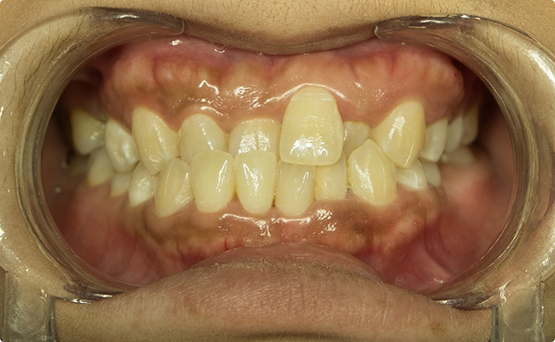

Case 1

Adult female, anterior and posterior crossbite, crowded arches, and worn dentition.

Treatment: Patient was treated with Invisalign clear aligners only.